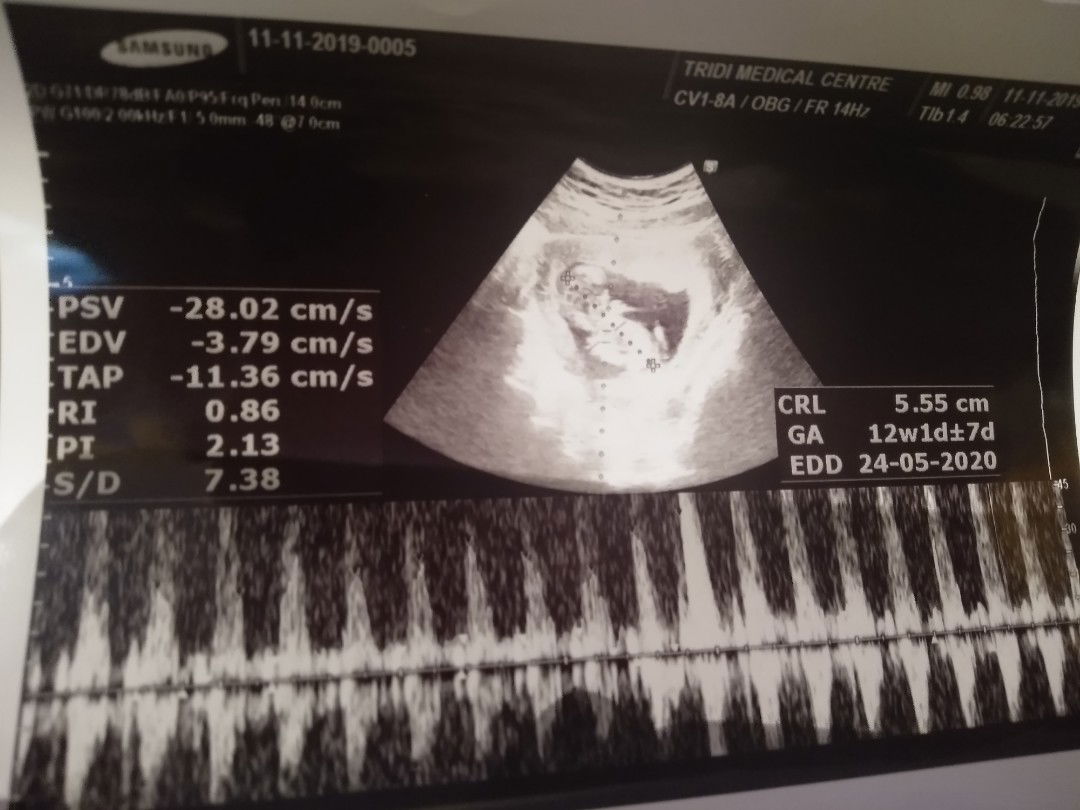

Hi mom, selamat malam. Adakah yg hamil muda tapi lg ngasuh anak balita jg? Mohon tipsnya mom cara redain mual, perut kembung sama kelelahan saat hamil muda dan harus ngasuh bocil 3 tahun tanpa ada org lain dirumah. Cuma bertiga sama papanya itupun papnya kerja pagi-malam 🙃#SeriusTanya #Sharing_dong_Bund